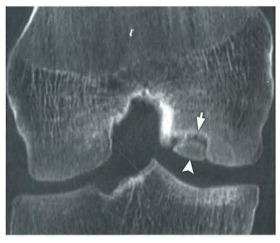

Tomografia do joelho abaixo demonstra falha óssea na face lateral do côndilo femoral medial (apontada pelas setas). O diagnóstico CORRETO é: